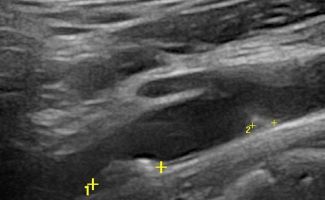

- Αθηρωματικές Πλάκες: Η ποιότητα και η σταθερότητα των αθηρωματικών πλακών είναι κρίσιμη για την πρόβλεψη του κινδύνου αποκόλλησης και εμφάνισης εγκεφαλικού επεισοδίου. Η εξέταση εντοπίζει αν οι πλάκες είναι μαλακές και ασταθείς.

- Ελαστογραφική Μελέτη: Εξετάζει την ελαστικότητα της αθηρωματικής πλάκας, διαπιστώνοντας αν είναι μαλακή και ασταθής, γεγονός που μπορεί να επηρεάσει την πιθανότητα αποκόλλησης και να έχει σαν επακόλουθο ισχαιμικό εγκεφαλικό επεισόδιο.